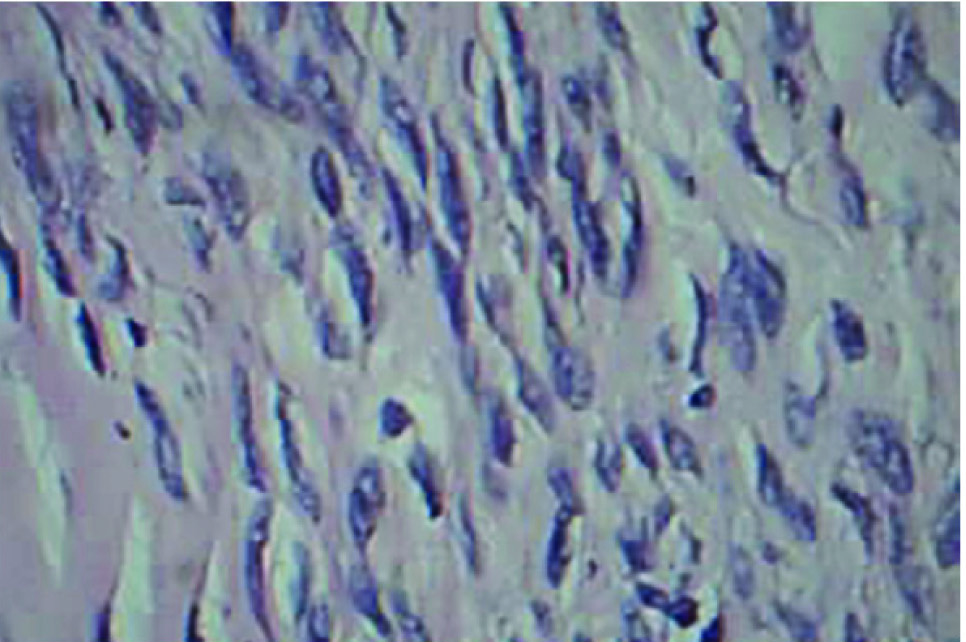

On gross examination, the ovarian mass was measuring 16 × 11 × 12 cm and the cut section of tumour showed hard grey white solid area which was well encapsulated. Microscopically, it showed well encapsulated benign tumour composed of fascicles and interlocking bundles of smooth muscles of fibres with blunt ended nuclei [Table/Fig-4a & b]. Large areas of sclerosis were seen. Thickened blood vessels with areas of haemorrhage were noticed. No cellular atypia was made out. Mitotic activity was sparse, 0-1/10 high-power field. Staining with masson’s trichrome stain showed positivity for smooth muscle fibres [Table/Fig-5]. The uterine endometrium showed senile cystic hyperplasia. Cervix, bilateral tubes and right ovary were unremarkable. Based on these findings, a diagnosis of ovarian leiomyoma was made out.

Microscopy view of ovarian leiomyoma after H &E stain showing spindle cell- intersecting bundles of smooth muscle cell(40x)

Masson’s trichrome staining showing positivity for smooth muscle cells(red)

The differential diagnosis for ovarian leiomyoma include ovarian fibroma, thecoma, cellular fibroma and sclerosing stromal tumour [8–10] As all these tumours exhibit similar type of clinical picture, histopathological examination plays an important role in the diagnosis. The correct diagnosis of ovarian leiomyoma requires the confirmation of smooth muscle component of the tumour. Masson’s trichrome staining helps to distinguish fibrous and smooth muscle components of the lesion [9,11,12]. and confirms the diagnosis of ovarian leiomyoma. Usually, ovarian leiomyomas have a benign course. Complete surgical resection is the treatment of choice [4].